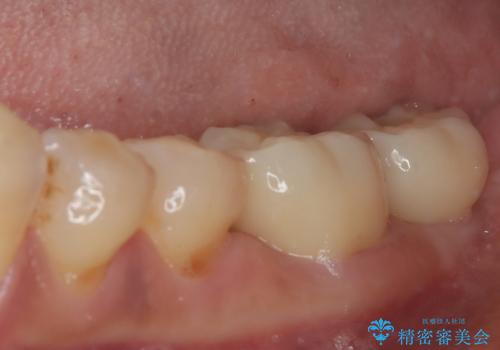

骨よりも深く進行したむし歯 即時荷重インプラントでの短期間治療

- 左下奥のクラウンに違和感を感じるとのことで来院された患者様です。

最後方歯は歯槽骨よりも深い部分にまでむし歯が及んでおり、患者様と相談の上、インプラントによる補綴治療を行うこととしました。

手前の歯は、適合の悪いクラウンを最後方歯と同時にオールセラミッククラウンにて補綴治療を行うこととしました。

骨の高さが不十分であったため、インプラント強度を維持しながらも高さの小さいインプランを使用しました。